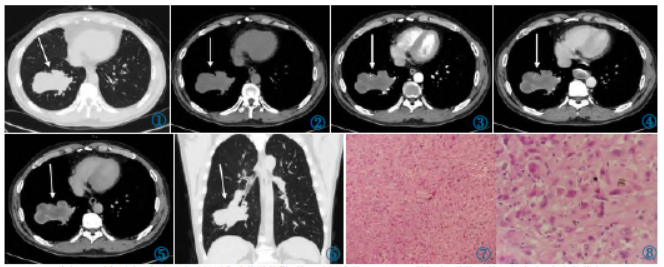

图1胸部CT平扫肺窗:右肺下叶不规则分叶状肿块影(箭),边界清楚。图2纵隔窗:肿块呈软组织密度,密度较均匀。图3~5CT增强:肿块呈不均匀边缘明显强化,动脉期即开始呈边缘明显强化,静脉期强化程度进一步增加,延迟120s病灶强化最明显。图6冠状位MPR重组:右肺下叶支气管截断。图7镜下瘤细胞呈明显的多形性、异型性,以纤维母细胞和圆形组织样细胞为主,肥胖的梭形细胞排列呈车辐状(HE)。图8镜下瘤细胞多形性明显,见核分裂像及瘤巨细胞(HE)。

冠状位MPR重组示右肺下叶支气管截断(图6)。气管镜检查:右肺下叶开口

影像学特点:肿块表现为体积较大的实性肿物,周围型多见,好发于中下肺,呈类圆形分叶状,边界较清晰,周围毛刺少见。平扫密度不均,内部多有囊变、坏死,可合并出血,极少数伴有钙化,病变具有侵袭性,可侵犯血管、胸膜、胸壁等邻近组织结构,增强扫描肿瘤实性部分较明显强化,纵隔及肺门淋巴结转移少见,可发生远处转移。